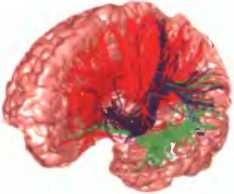

Дофаминовые связи

Дофаминовые проводящие пути проходят, извиваясь, по всему головному мозгу, в разных местах выполняя разные функции. В глубине ствола мозга, в структуре, называемой черной субстанцией, располагаются производящие дофамин нейроны, стимулирующие и поддерживающие нашу активность, физическую и умственную. Когда эти клетки дегенерируют, как при болезни Паркинсона, человек теряет способность уверенно шагать вперед — как в прямом, так и в переносном смысле.

Другой комплекс дофаминовых путей называют “системой вознаграждения” нашего мозга. Они ведут от вентральной области покрышки к миндалине, прилежащему ядру, септуму и префронтальной коре (все эти структуры вместе называют медиальным пучком переднего мозга). Стимуляция прилежащего ядра дофамином запускает приготовление нашего тела к тому, чтобы схватить желанный объект или пуститься за ним в погоню, в то время как миндалина определяет ценность этого объекта и способствует возникновению осознанного ощущения возбуждения, а префронтальная кора и септум концентрируют наше внимание на намеченной цели. Все вместе эти реакции создают у нас приподнятое настроение. Однако они не рождают чувство длительного удовлетворения, и если дофаминовая система работает без посредничества других нейромедиаторов, вслед за выбросом дофамина обычно возникает потребность в еще одном таком выбросе, а вслед за ним — в еще одном. Этот механизм лежит в основе психологического привыкания.